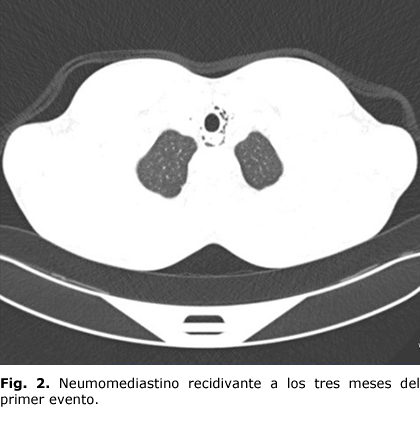

Tres meses más tarde acude nuevamente a consulta por presentar dolor torácico opresivo, disfagia y disnea, además de tos productiva. Al examen físico se encontró crepitación a la palpación de la zona superoanterior del tórax y cuello (enfisema subcutáneo). Es discutido nuevamente con los cirujanos de tórax y se le indica el TAC de tórax simple y contrastado por la posibilidad de un nuevo neumomediastino, se observa aire en tejido celular subcutáneo del cuello; y en menor cantidad que en el estudio anterior, a nivel de las regiones axilares y del mediastino, donde es visible más hacia mediastino posterior, decolando aorta y esófago y algo hacia ramas secundarias de la arteria pulmonar izquierda y penetra además en la gran cisura izquierda (Fig. 2). Se decide realizar broncoscopía y se observa la tráquea, carina, árbol bronquial izquierdo y árbol bronquial derecho con enrojecimiento de toda la mucosa traqueobronquial asociado a incremento de secreciones purulentas.